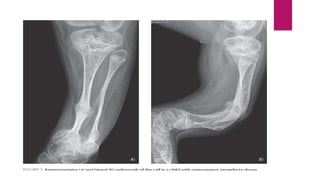

Radiological features

 Cortices of long bones are often thin and demonstrate features of generalized demineralization.

 Severe forms- bones are thick and short with multiple fractures and hyperplastic callus formation.

 Skull is osteopenic and multiple intrasutural wormian bones are present.

 Multiple rib fractures.

 Protrusio acetabuli and proximal femoral shepherd’s crook deformity

 Multiple areas of radiolucent scalloping with radio-dense rims with the appearance of popcorn

can be seen in the metaphysis